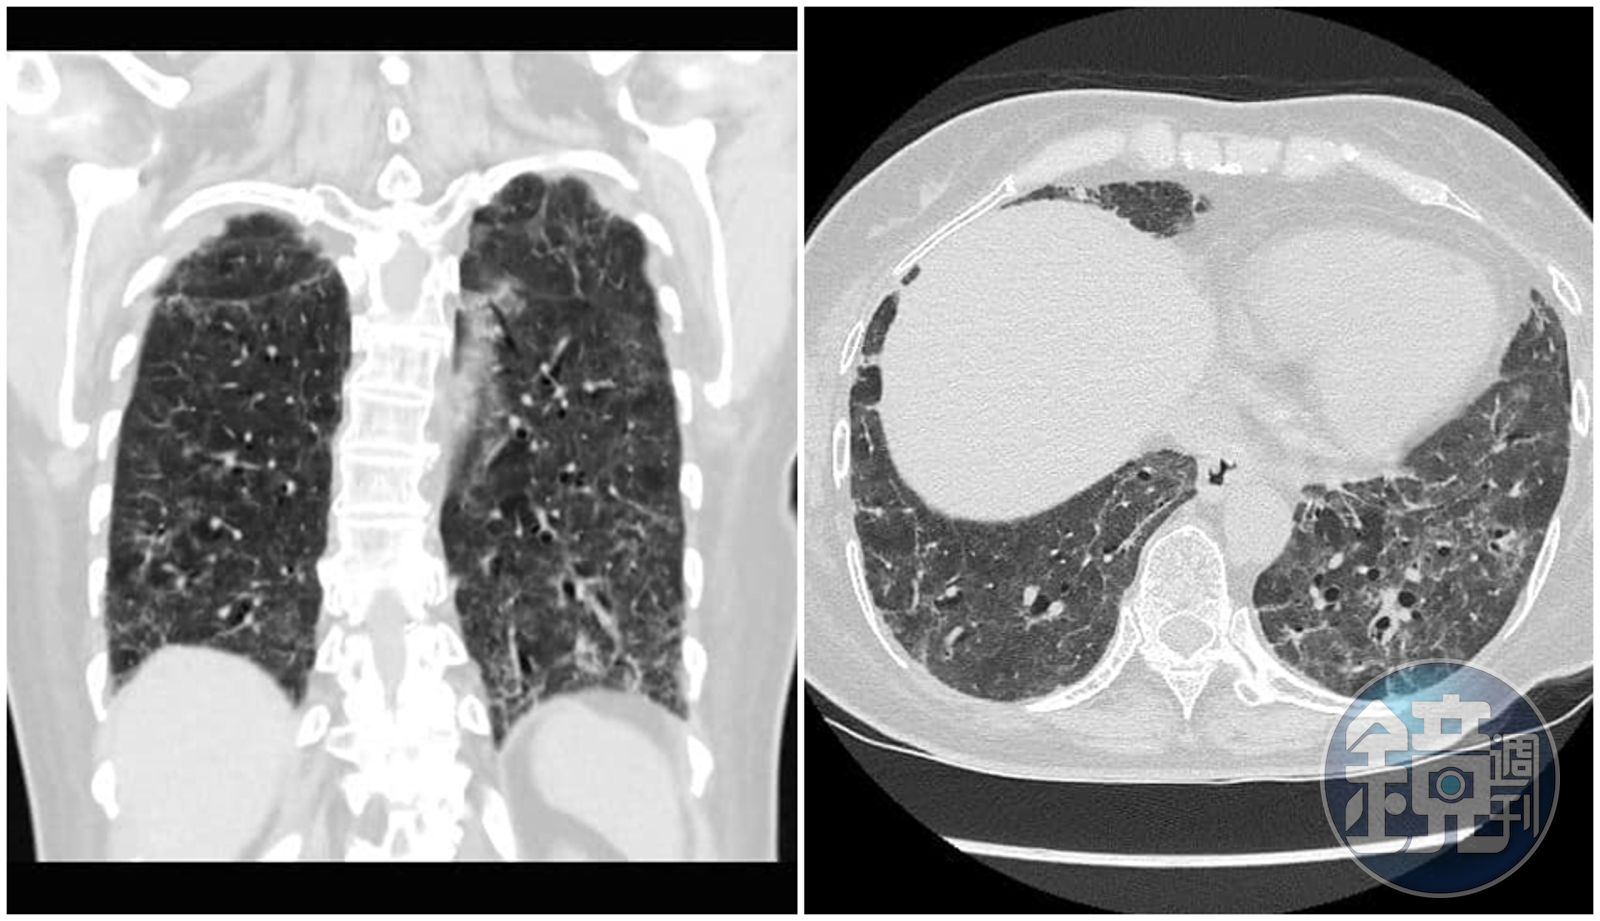

醫師蘇一峰今天在臉書貼出COVID-19確診重症病患「肺纖維化」的照片,表示病人現在無法脫離氧氣,而這樣的情況出現在院內自己人身上,讓他非常難過,還透露昨天打了好幾通電話想辦法。

蘇一峰心痛呼籲,「高危險醫護人員趕快打疫苗,不想肺纖維化就趕快打疫苗」,他也在留言處表示,很多醫護人員第一劑都是打AZ疫苗,要等2個月才能打第二劑,有些醫護等待的中間就被感染了,如果可以混打只要等1個月就好。」

(取自蘇一峰臉書)